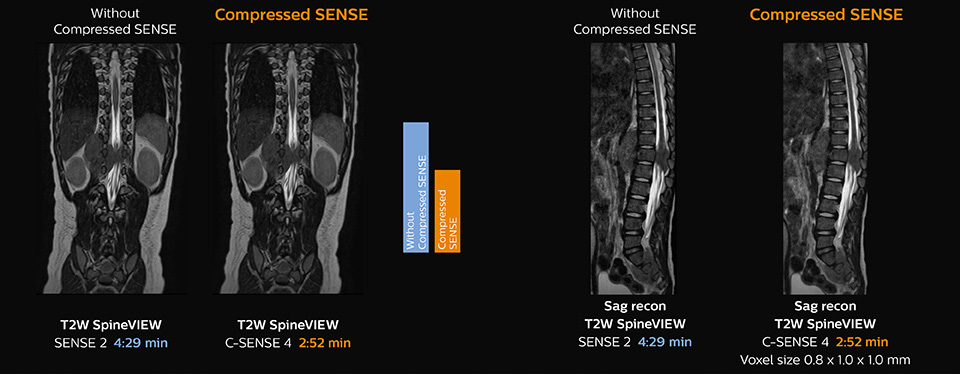

Boosting diagnostic confidence with multiple contrasts, multiple orientations in spine MRI

“Previously with SENSE, our 2D mDIXON TSE scans required relatively long scan times. But now, with Compressed SENSE, we have reduced these scan times while maintaining a high SNR, because the Compressed SENSE technology helps reduce noise,” says Dr. Koyama. “Because the faster scanning with Compressed SENSE saves us time, we can sometimes add a sequence to obtain high quality spine images in the same time slot for confident diagnoses. And in cervical spine exams, a 2D sequence is sometimes replaced by a 3D protocol, which provides us more information as it can be reformatted in different orientations. Compressed SENSE allows us to easily add this 3D sequence in the timeslot,” says Fukushima “Incorporating Compressed SENSE in common spine sequences, such as mDIXON, 3D SpineVIEW and eTHRIVE, can substantially reduce the scanning time of these sequences, while maintaining adequate spatial resolution, resulting in high quality, multiple contrasts, multiple orientations,” says Dr. Koyama. “In addition, fast sequences generally make it easier for patients to stay motionless throughout the scans, so it also helps us in that way.”

The KCH team has already changed most of their Ingenia 1.5T spine ExamCards by incorporating Compressed SENSE into their 2D TSE, mDIXON TSE, FFE, and 3D sequences.

As this was one of the first patients scanned with Compressed SENSE, 3D SpineVIEW was acquired with and without Compressed SENSE to allow comparison. Although the Compressed SENSE sequence was significantly faster, the acquired and reconstructed 3D SpineVIEW images show virtually the same image quality.